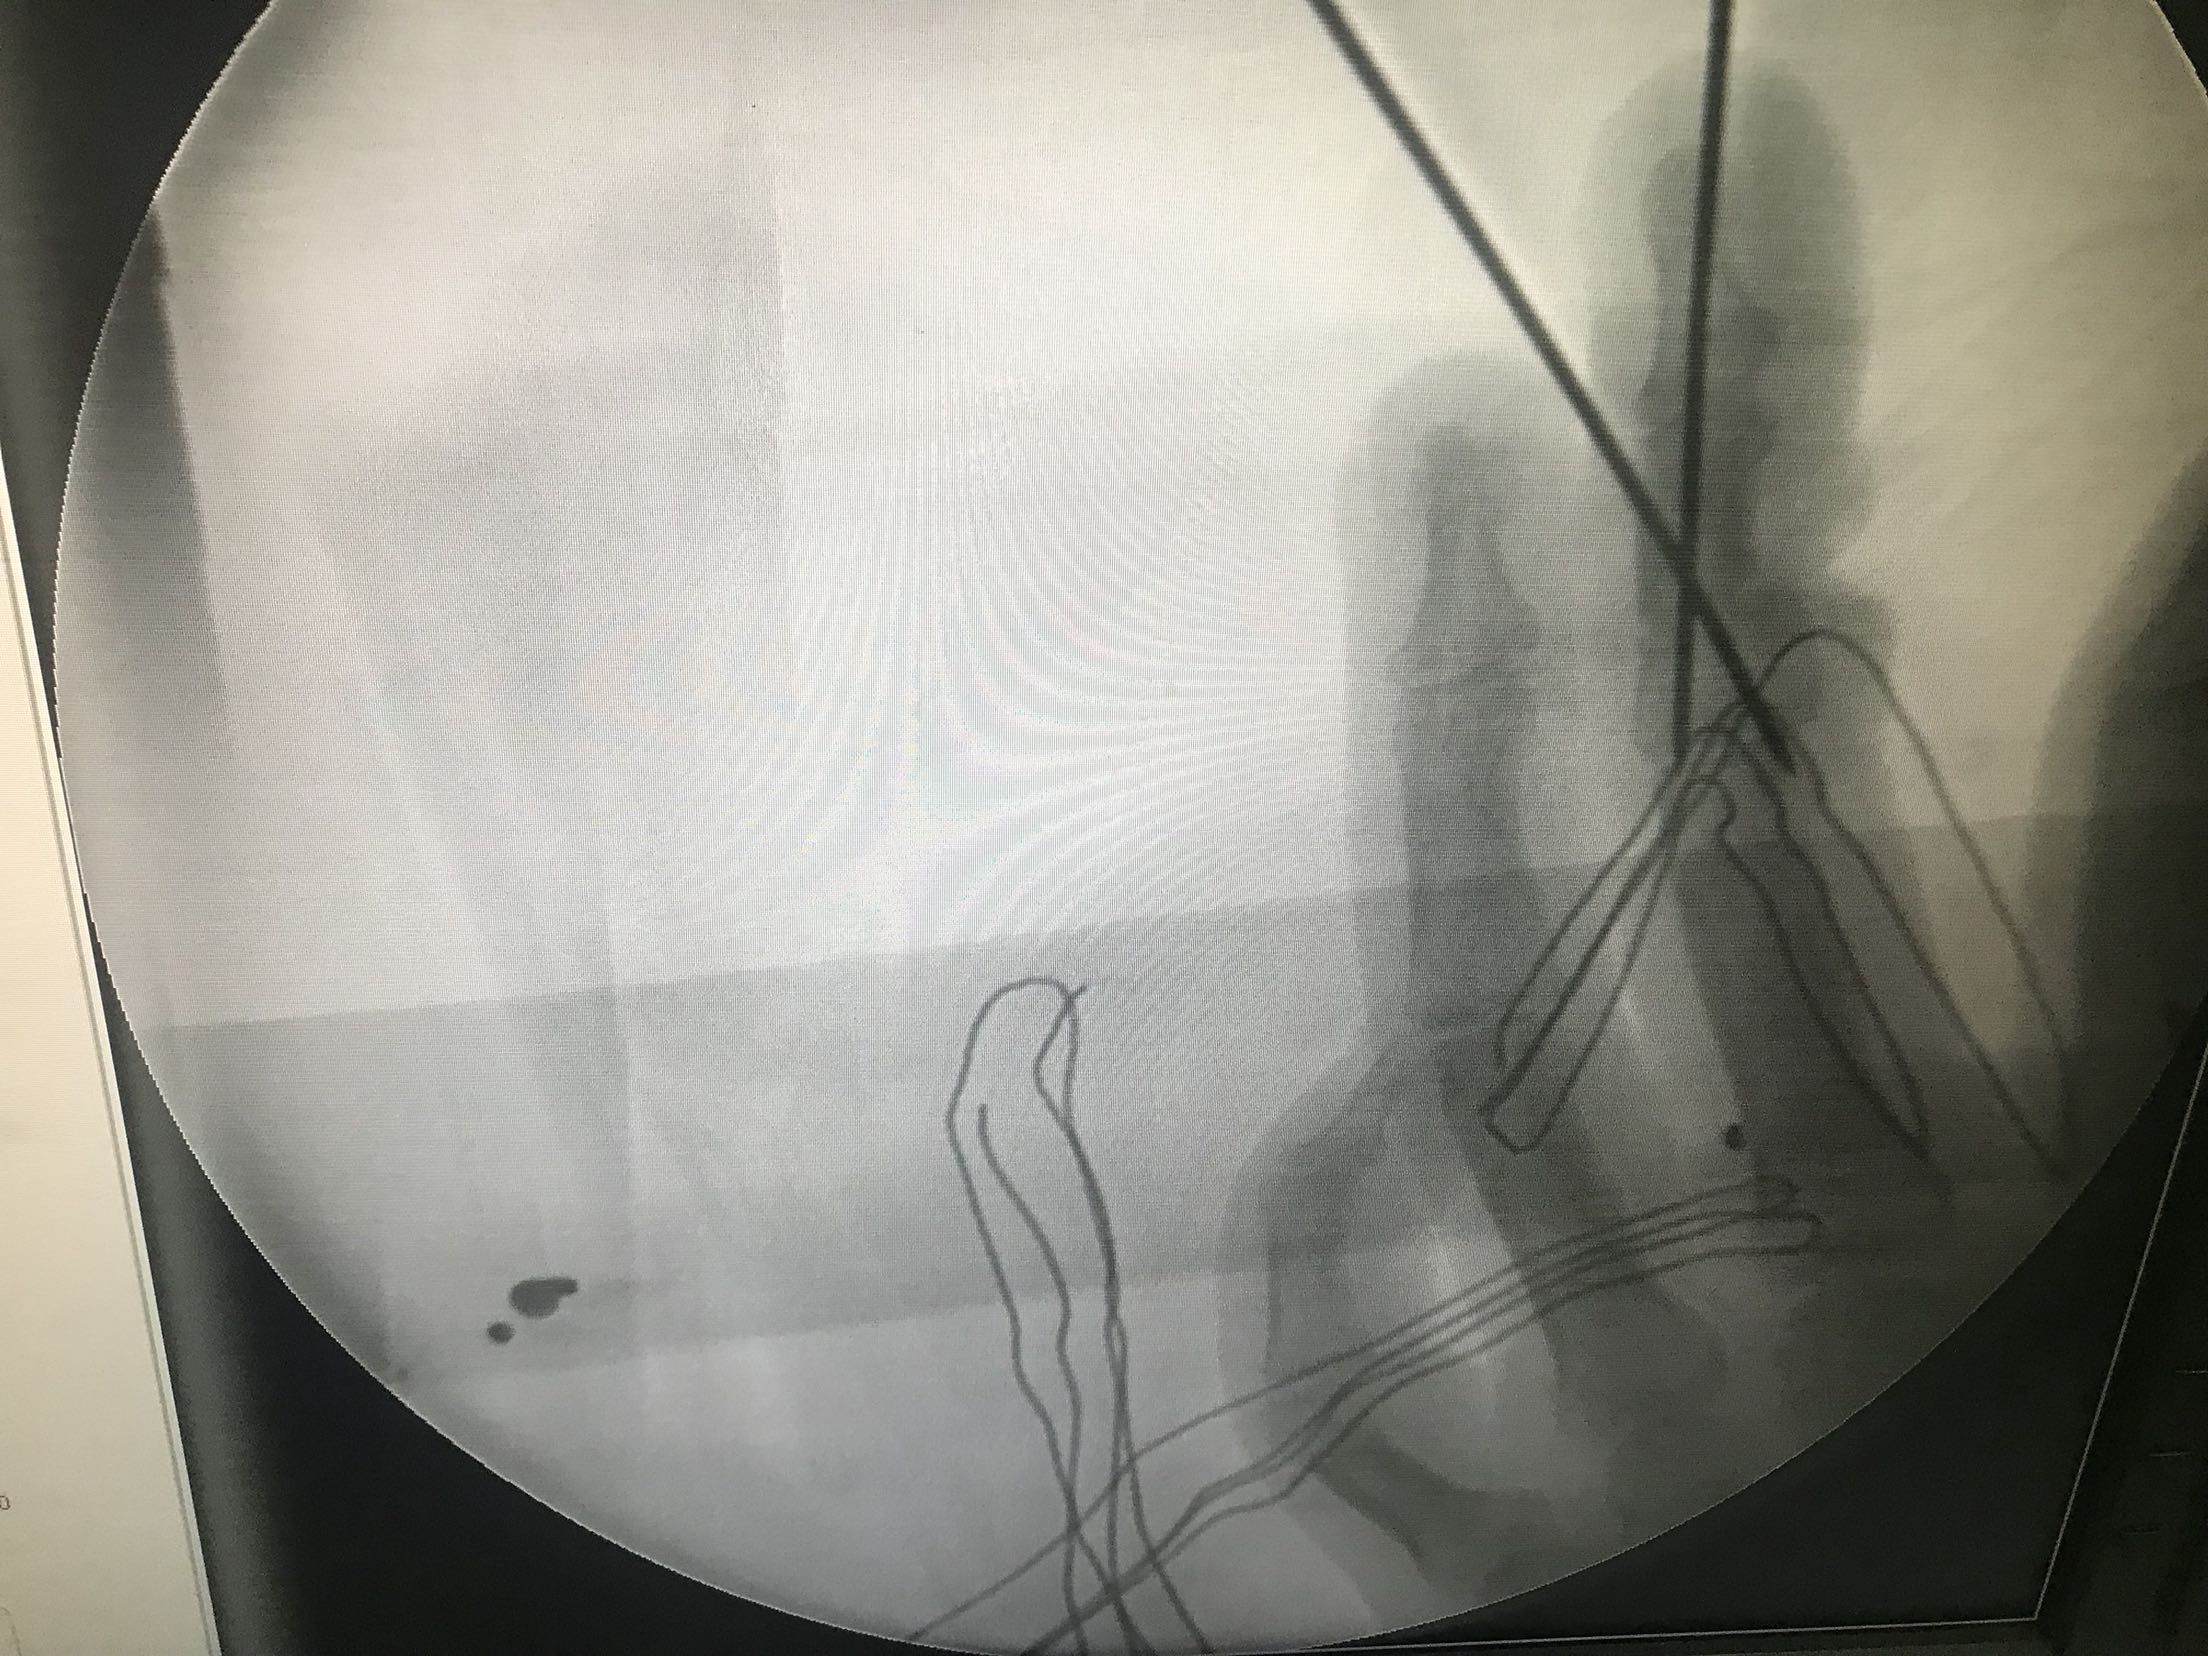

右手中指中节指体半环形锯齿状离断创口,创缘不齐,挫伤严重。仅尺侧部分皮肤软组织相连。离断指体颜色苍白,无血运,无温度,无感觉。

右手中指不全离断伤。急诊在臂丛麻醉下行右手中指试行再植术。术中适当短缩骨质,复位后克氏针内固定,修复屈伸肌腱,吻合双侧动脉神经。